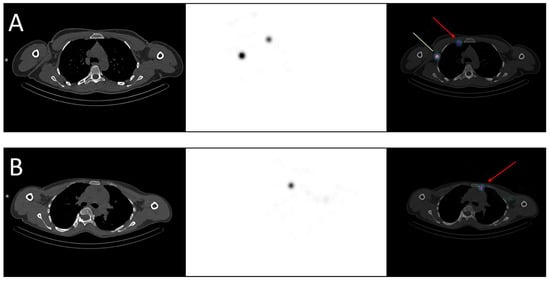

- Hinsenveld, F.J.; Wit, E.M.K.; van Leeuwen, P.J.; Brouwer, O.R.; Donswijk, M.L.; Tillier, C.N.; Vegt, E.; van Muilekom, E.; van Oosterom, M.N.; van Leeuwen, F.W.B.; et al. Prostate-Specific Membrane Antigen PET/CT Combined with Sentinel Node Biopsy for Primary Lymph Node Staging in Prostate Cancer. J. Nucl. Med. 2020, 61, 540–545. [Google Scholar] [CrossRef]

- Doughton, J.A.; Hofman, M.S.; Eu, P.; Hicks, R.J.; Williams, S. A First-in-Human Study of 68Ga-Nanocolloid PET/CT Sentinel Lymph Node Imaging in Prostate Cancer Demonstrates Aberrant Lymphatic Drainage Pathways. J. Nucl. Med. 2018, 59, 1837–1842. [Google Scholar] [CrossRef]

- Michaud, A.V.; Samain, B.; Ferrer, L.; Fleury, V.; Doré, M.; Colombié, M.; Dupuy, C.; Rio, E.; Guimas, V.; Rousseau, T.; et al. Haute Couture or Ready-to-Wear? Tailored Pelvic Radiotherapy for Prostate Cancer Based on Individualized Sentinel Lymph Node Detection. Cancers 2020, 12, 944. [Google Scholar] [CrossRef]